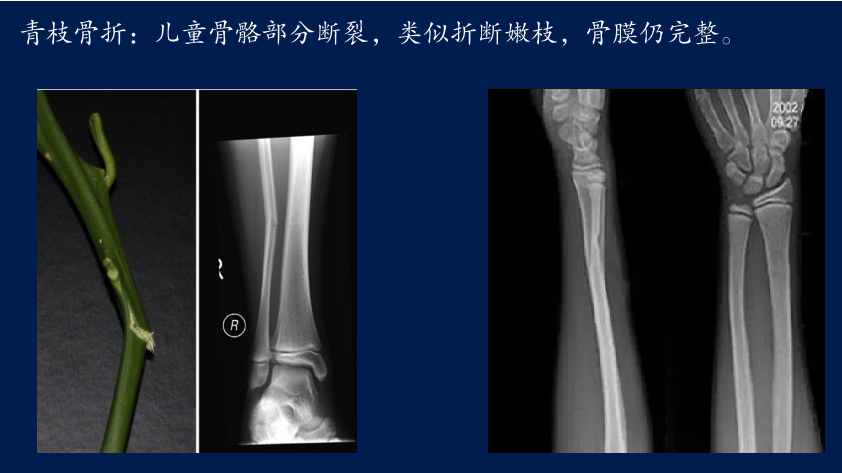

不同种类的骨折您了解多少